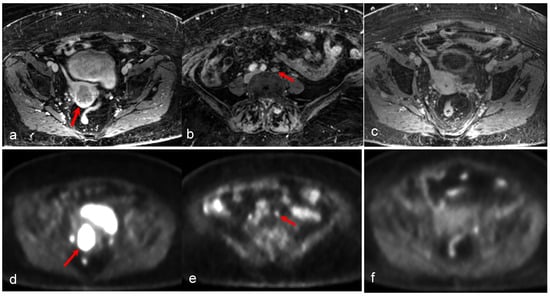

3.2. Endometrial Cancer

- Tsuyoshi, H.; Tsujikawa, T.; Yamada, S.; Chino, Y.; Shinagawa, A.; Kurokawa, T.; Okazawa, H.; Yoshida, Y. FDG-PET/MRI with high-resolution DWI characterises the distinct phenotypes of endometrial cancer. Clin. Radiol. 2020, 75, 209–215. [Google Scholar] [CrossRef] [PubMed]

- Tsuyoshi, H.; Tsujikawa, T.; Yamada, S.; Okazawa, H.; Yoshida, Y. Diagnostic value of 18F-FDG PET/MRI for staging in patients with endometrial cancer. Cancer Imaging 2020, 20, 75. [Google Scholar] [CrossRef]

- Kitajima, K.; Suenaga, Y.; Ueno, Y.; Kanda, T.; Maeda, T.; Takahashi, S.; Ebina, Y.; Miyahara, Y.; Yamada, H.; Sugimura, K. Value of fusion of PET and MRI for staging of endometrial cancer: Comparison with ¹⁸F-FDG contrast-enhanced PET/CT and dynamic contrast-enhanced pelvic MRI. Eur. J. Radiol. 2013, 82, 1672–1676. [Google Scholar] [CrossRef]

- Ironi, G.; Mapelli, P.; Bergamini, A.; Fallanca, F.; Candotti, G.; Gnasso, C.; Taccagni, G.L.; Sant’Angelo, M.; Scifo, P.; Bezzi, C.; et al. Hybrid PET/MRI in Staging Endometrial Cancer: Diagnostic and Predictive Value in a Prospective Cohort. Clin. Nucl. Med. 2022, 47, e221–e229. [Google Scholar] [CrossRef]